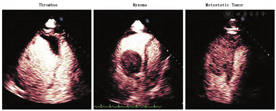

在进行超声灌注显像时使用VLMI间歇性闪击(high-MI)技术,可以显示心脏占位的血管特征,帮助鉴别其为血流丰富的恶性肿瘤还是良性肿瘤,或血栓[76]。不同类型心脏占位灌注(增强)程度的定性和定量差异,以及与邻近心肌的对比,均可为这种血管特征提供鉴别依据。定性的方法包括肉眼判断高MI闪击后包块内增强剂恢复的速率,可分为:无增强、部分或不完全增强、完全增强[76]。大多数恶性肿瘤都分布有异常新生血管以供应肿瘤细胞的快速生长,通常以密集、扩张的血管形式出现[77]。因此,肿瘤的完全增强或过度增强(对比周围心肌)提示多血管肿瘤的存在,而多血管肿瘤通常是恶性的[77]。间质肿瘤的血液供应不足,呈部分增强(如黏液瘤)(视频5和图2;在www.onlinejase.com获取),而血栓或乳头状弹性纤维瘤一般无血管分布,无增强[78]。增强程度与病理诊断或抗凝治疗后团块的消退相关[77],然而,潜在的缺点是可能导致远场无血管结构呈部分增强。因此,建议灌注成像应在可近场观察高MI闪击后微泡再灌注的切面进行。自2008年ASE共识发表以来的几项研究也证实了VLMI结合高MI闪击时不同病理类型心内占位的最大声强和再灌注速度之间的差异[79,80]。